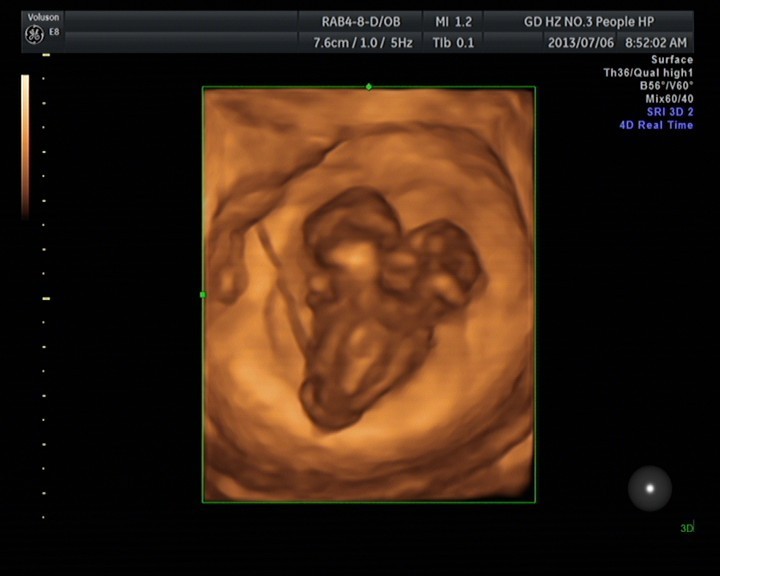

隨著環(huán)境污染日益嚴重,隨著各種地溝油的誕生,隨著各樣鎘大米的泛濫……我們的健康越來越受到威脅,很多疾病也隨之接踵而至,胎兒先天性疾病也越來越多見。7月6日,我院超聲科王瑤醫(yī)生在做胎兒產(chǎn)前NT篩查中發(fā)現(xiàn)一例孕約11周+的聯(lián)體雙胎。超聲所見:增大的子宮內(nèi)可見聯(lián)體雙胎兒回聲,可見兩個胎頭不能分離,胸部及腹部融合,可見一個增大的心臟。

聯(lián)體嬰兒B超圖像